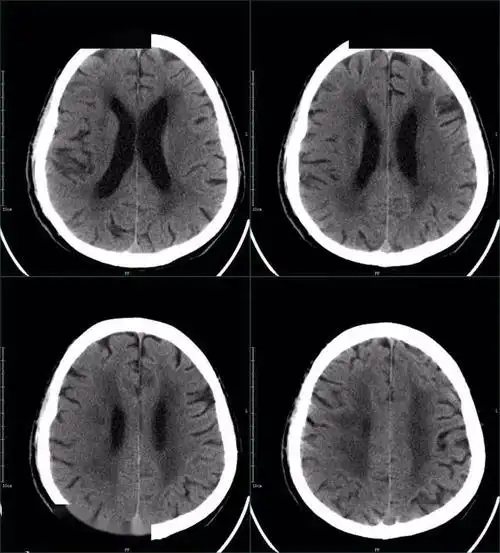

67超急性期大面积脑梗死ct平扫表现

图6. 2017年5月15日头颅ct显示脑沟脑池不清晰,脑肿胀明显.

图19:2015-4-19 ct:脑室系统正常